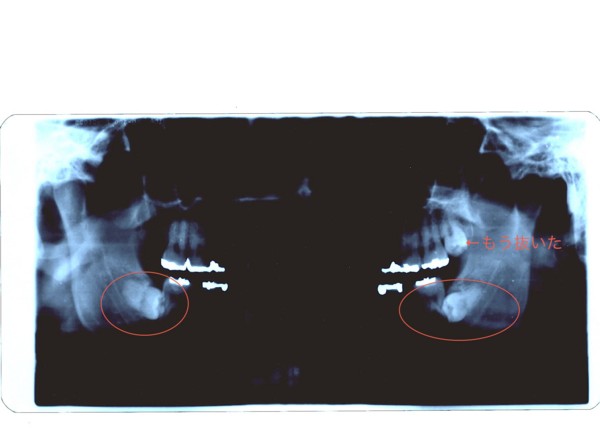

下の親知らずが水平埋伏智歯

かねてから、下の親知らずを抜くと腫れるとか痛いとか血みどろだとか、らしいのですが、私の場合はそれ以前の問題で、親知らずが埋まってる挙句横向いてるらしい...orz 水平に埋まってる親知らず(=親知らずのことを智歯というらしいですね) だから、水平埋伏智歯。そのまま。

大学病院とかいって処置されてくださいって、紹介状とレントゲンもらった...orz